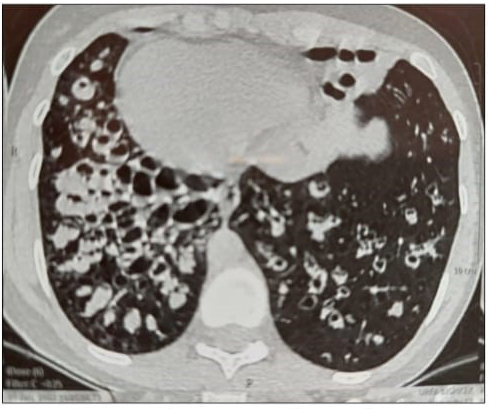

This 23 year old university student underwent left lung pneumectomy for large haemoptysis . He presented two years later with cough for one week and sore throat.

What is the abnormality seen on this chest Xray?

Question Image